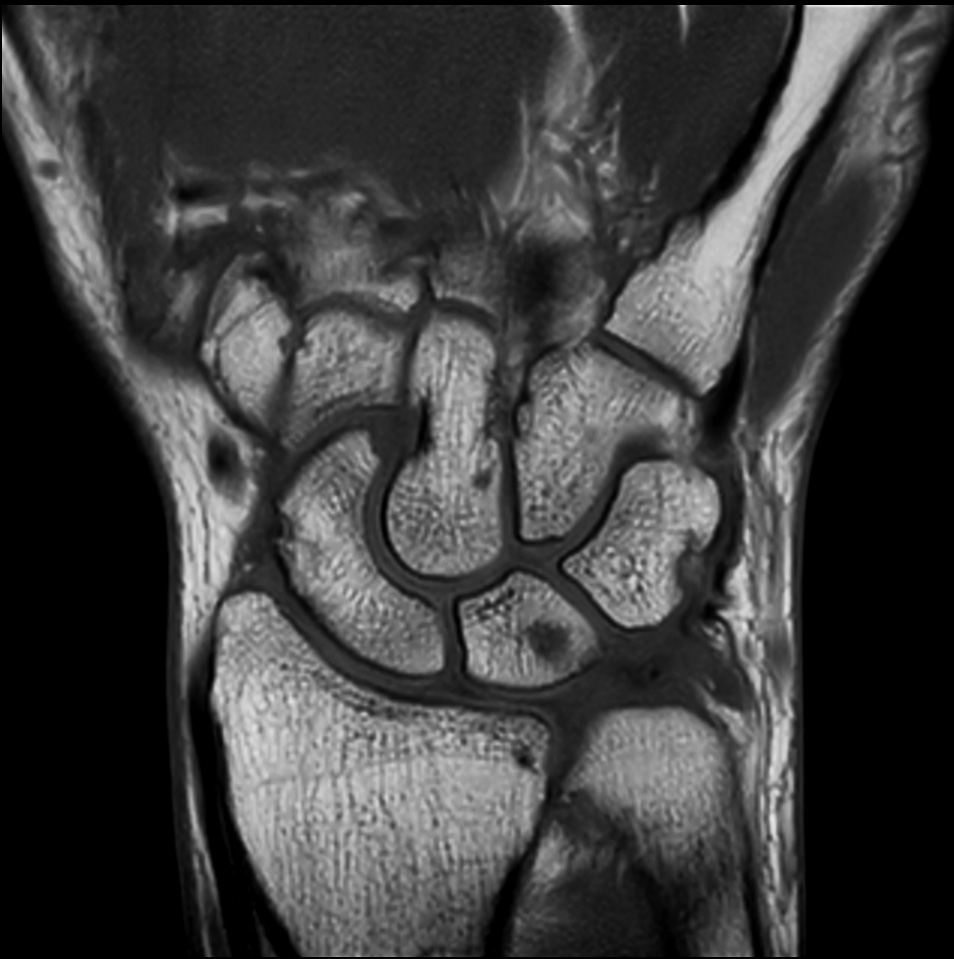

Comprehensive wrist imaging